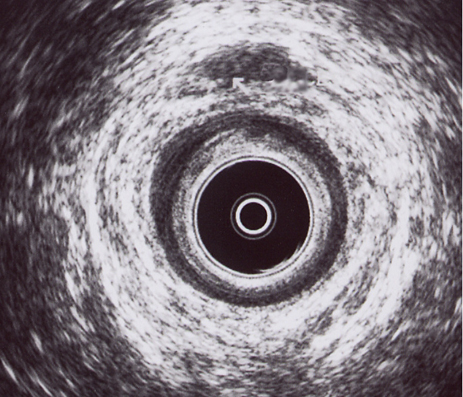

CANAL ANAL MEDIO: Imagen hipoecogénica anterior compatible con absceso anal anterior (flecha)